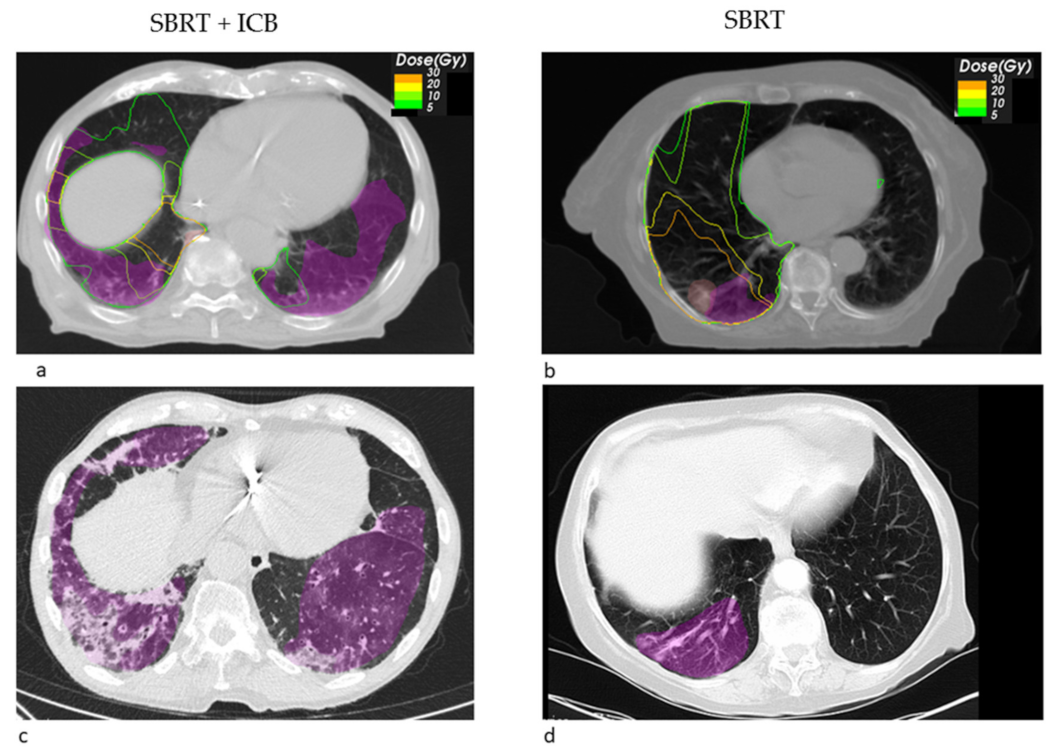

3. Results